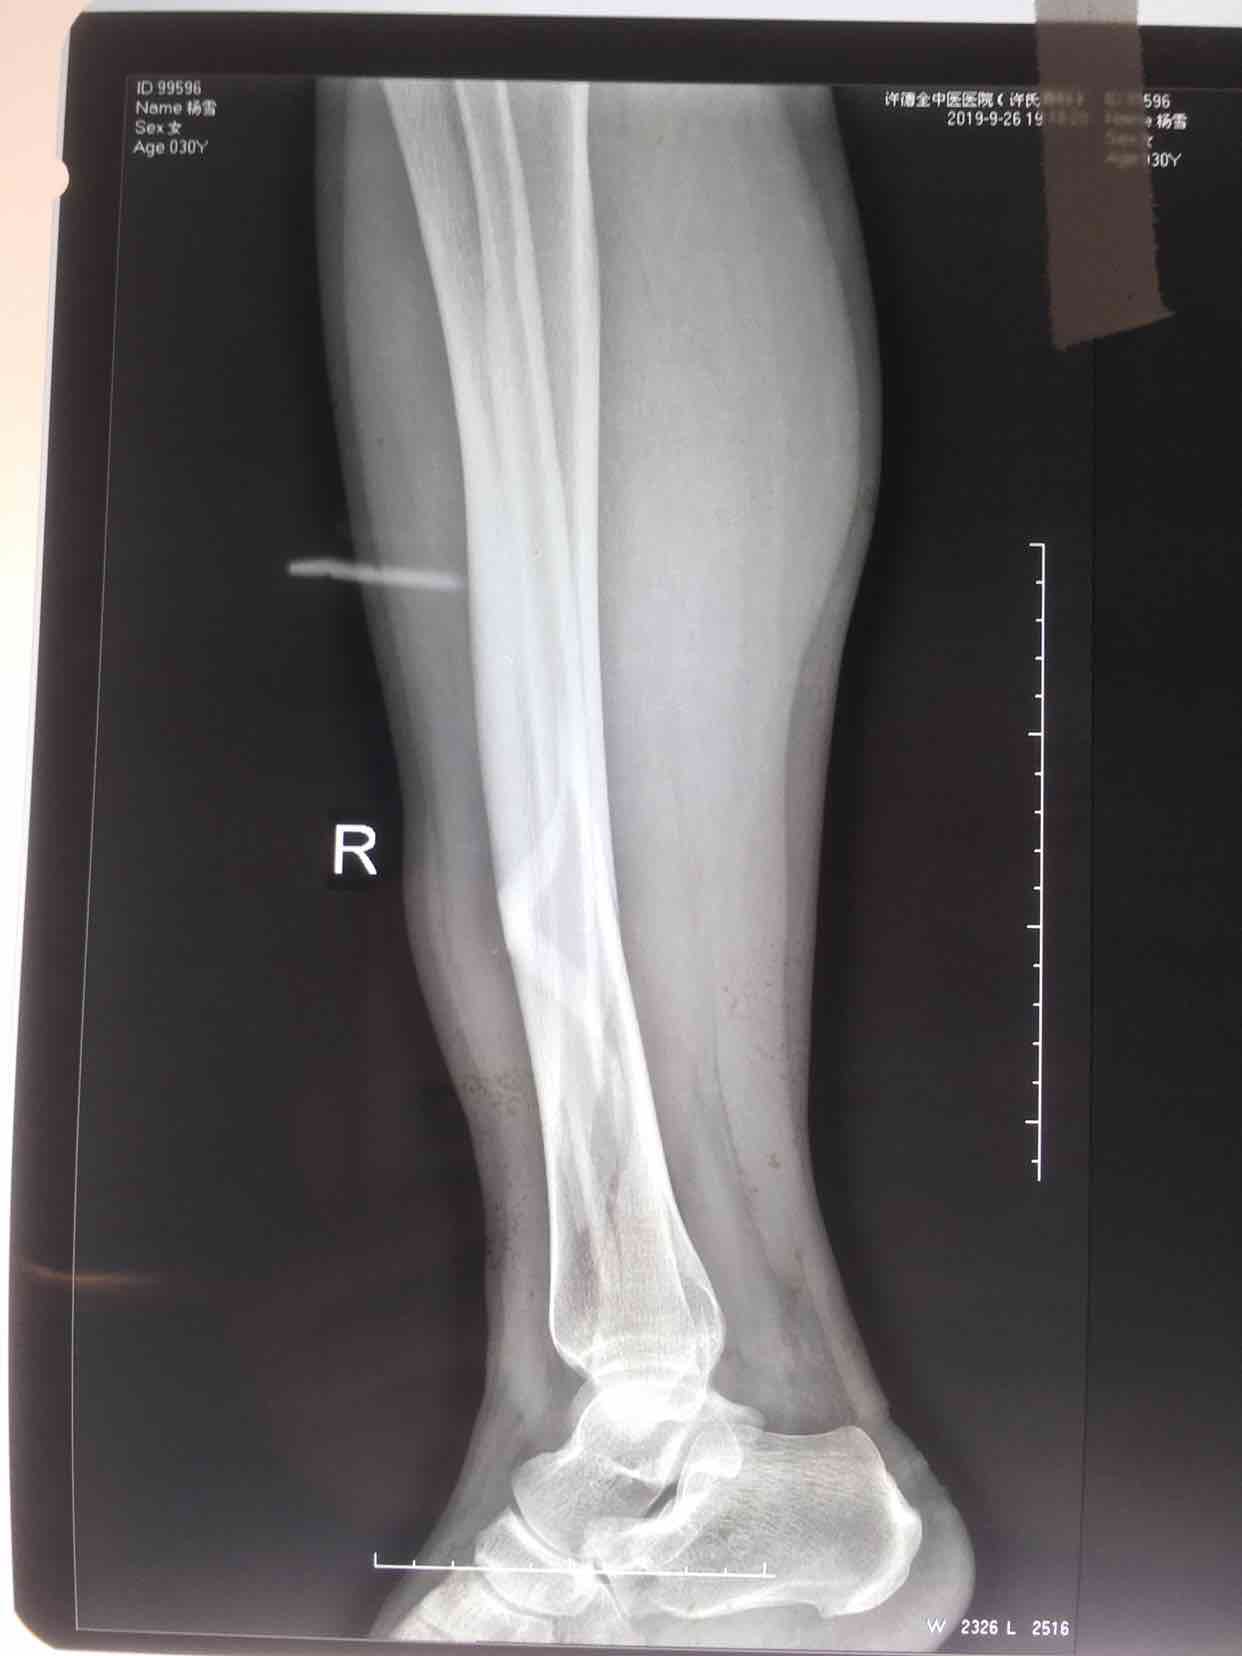

摔伤后右小腿肿胀,畸形,活动受限1小时入院。

生命体征平稳,心肺复未见异常。右小腿肿胀,畸形,局部皮温高,皮色发红,压痛及纵向叩击痛阳性,可及骨檫音及骨檫感,末梢血运感觉正常。

诊断右胫腓骨粉碎性骨折